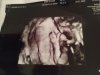

(znalazłam w Wawie lekarza, który robi USG 3D/4D i partner może być obecny podczas wizyty ) , więc chyba połączę jedno z drugim i zrobię wtedy od razu to trzecie USG

Mi lekarz powiedział, że na 3 USG można wykryć wady serca itd. Nie wiem, czy się zdecyduje. W pierwszej ciąży nie miałam.